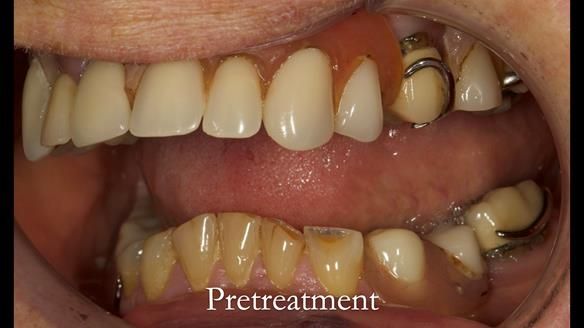

Aesthetically and functionally poor RPDs were replaced for Eileen, a 74 year old woman.

Referred to me by her general dental practitioner specifically for replacement RPDs.

Dental concerns

“Top denture loose making conversation difficult at times. Also, appearance isn’t good. Teeth uneven”

Diagnoses

- Missing teeth in the upper and lower jaws

- Upper and lower metal based RPDs, poorly fitting, worn occlusal surface, reverse curve aesthetics, lacking support

- Poor dental appearance with reverse incisal curve

- The upper right central and lateral incisors with post crowns. Healthy and functionally secure but with poor appearance, contributing to the reverse curve.

- Moderate to heavily restored dentition with deep overbite (Class 2 div II)

- Yellowish lower front teeth with small amount of wear.

- The lower right canine (LR3) is worn with MOD cavity.